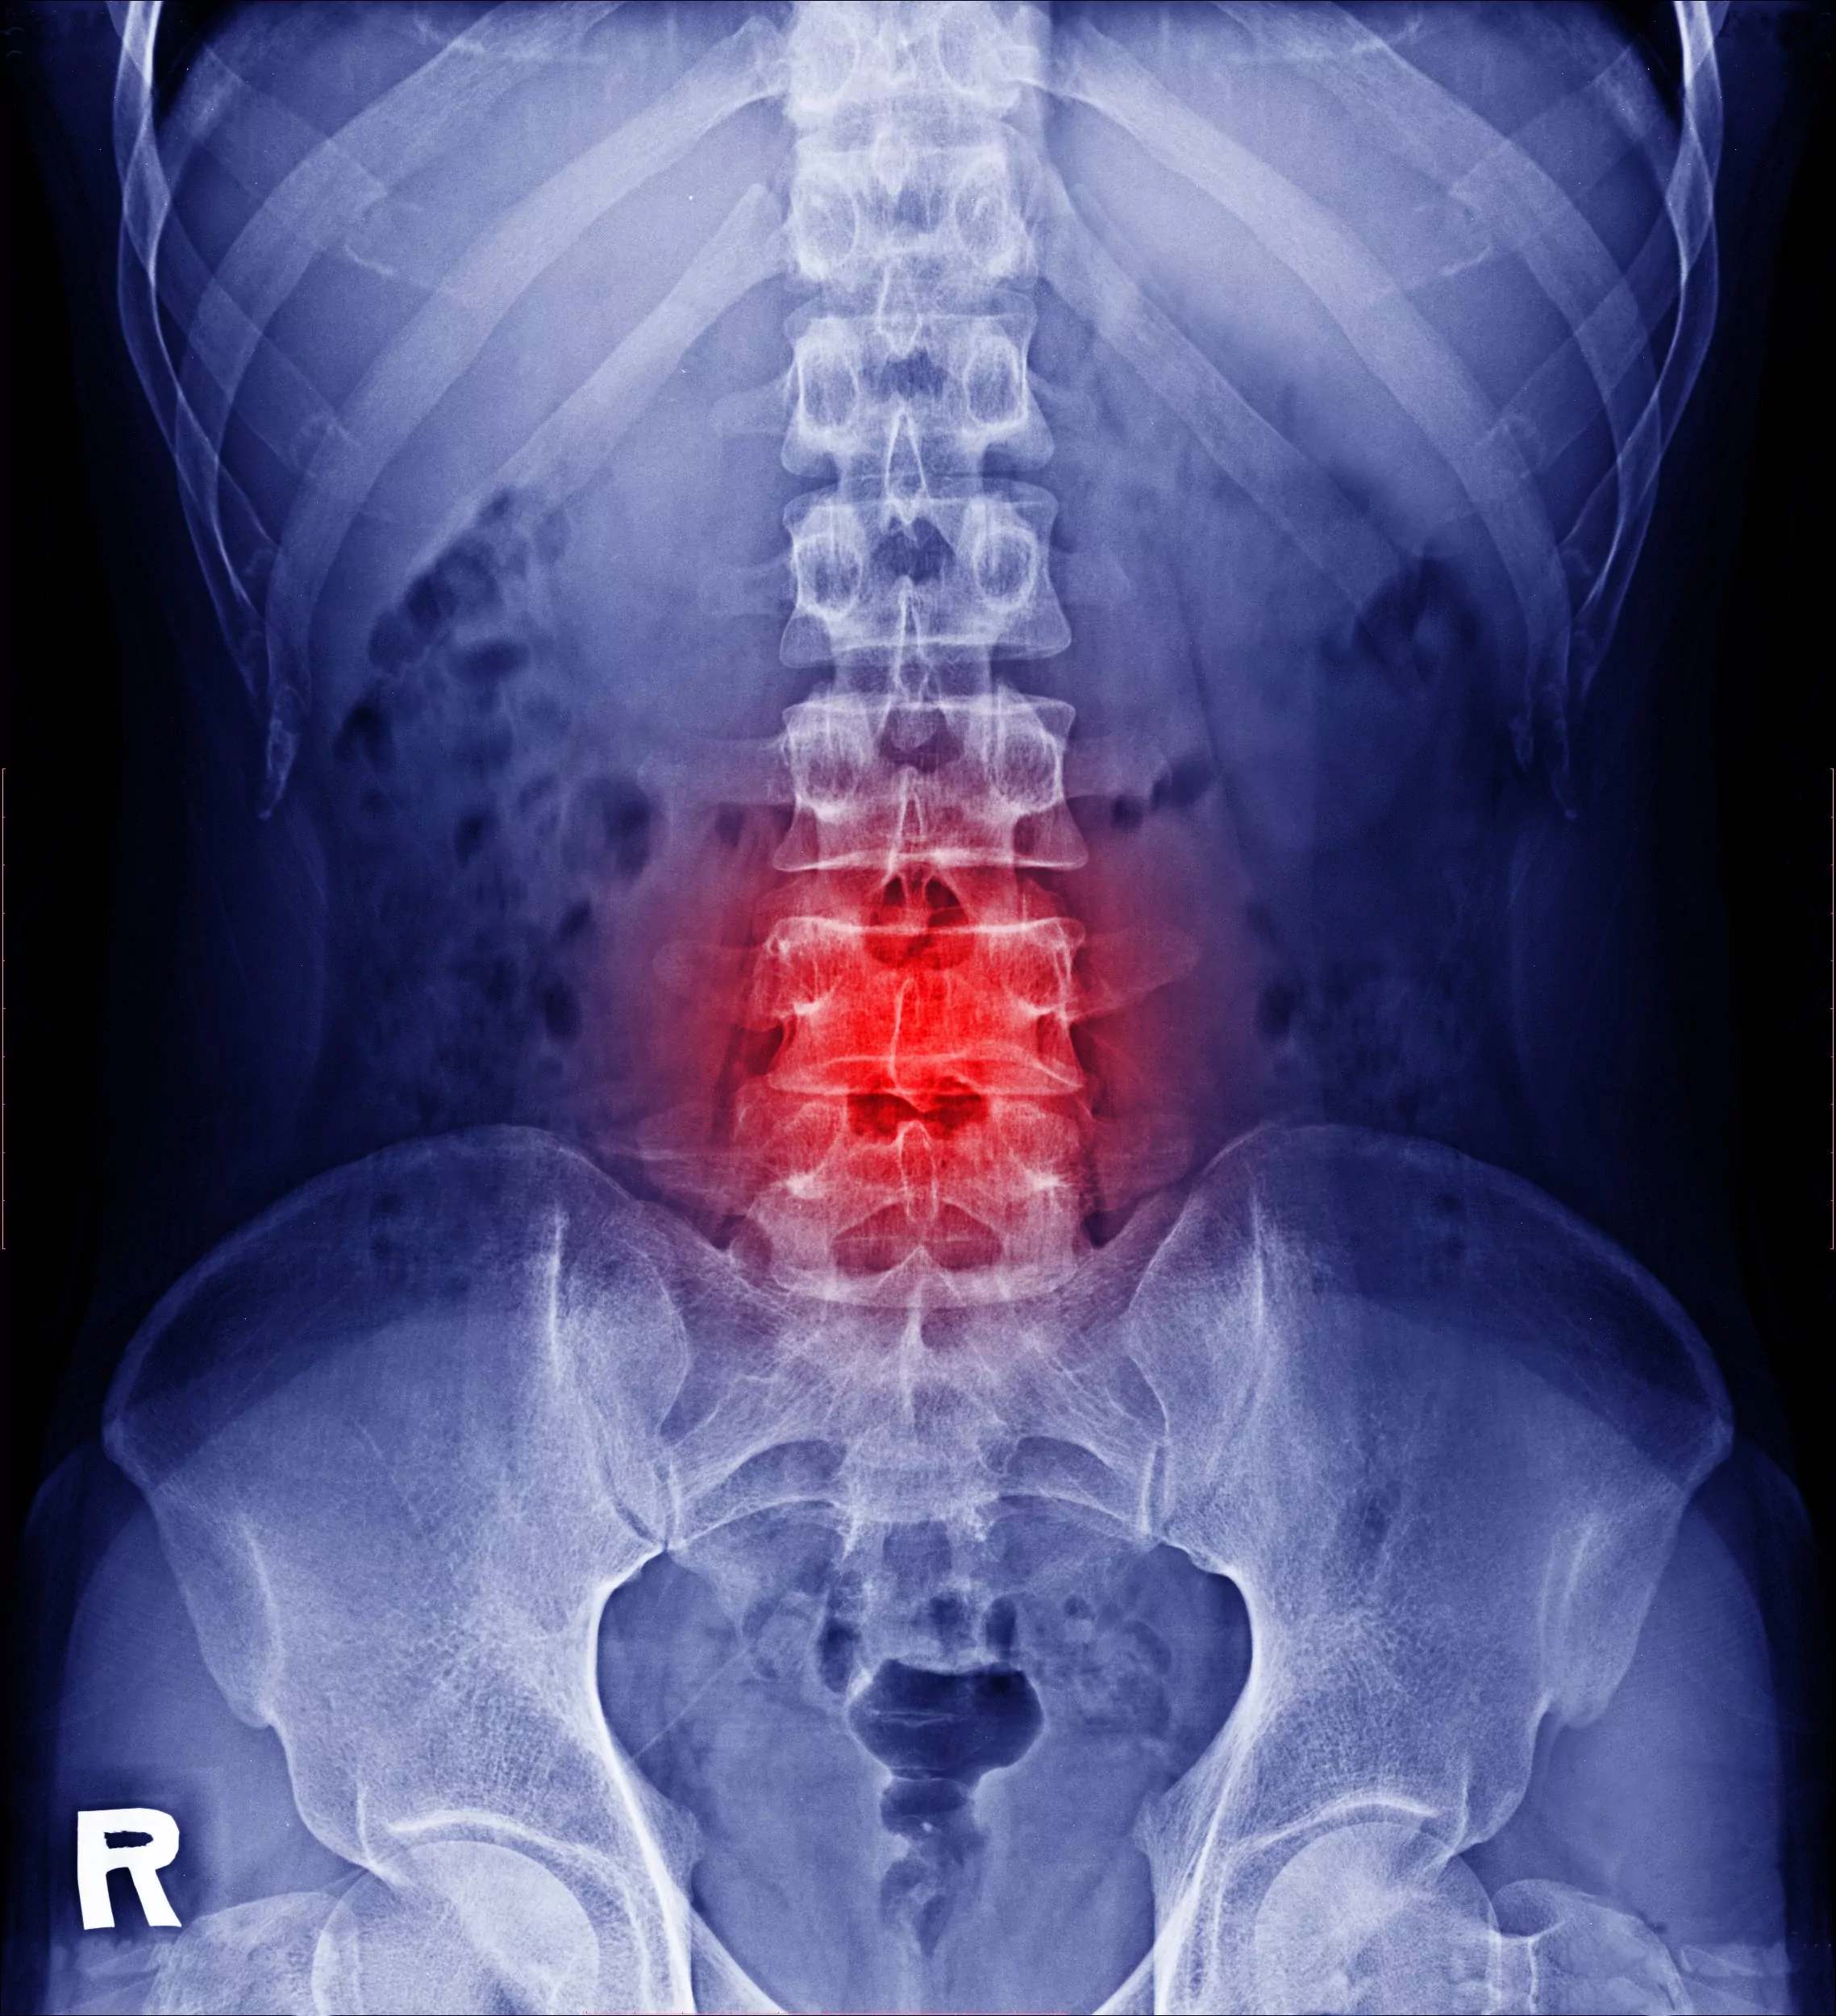

✔ Bulging or Herniated Lower Spinal Discs:

When you put continued stress on the "shock absorbing structures" in between the bony parts of your spine, they can start to shrink or perform in a way that isn't healthy. Think of your discs as balloons that are getting constantly squeezed in one direction all the time as you go about your day. The difference between bulging and herniated discs is usually the difference between the need for aggressive care or surgery (this can be determined via an exam and advanced imaging).